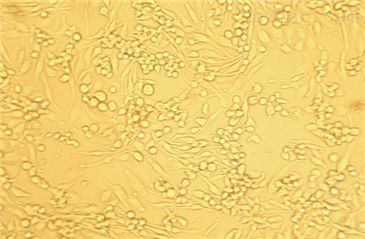

- 生长状态:

贴壁生长

有关KLM1(胰腺癌细胞)无菌技术:

KLM1(胰腺癌细胞)保证运输中细胞的正常生长,关于其价格、报价、货期,请咨询机纯生物。